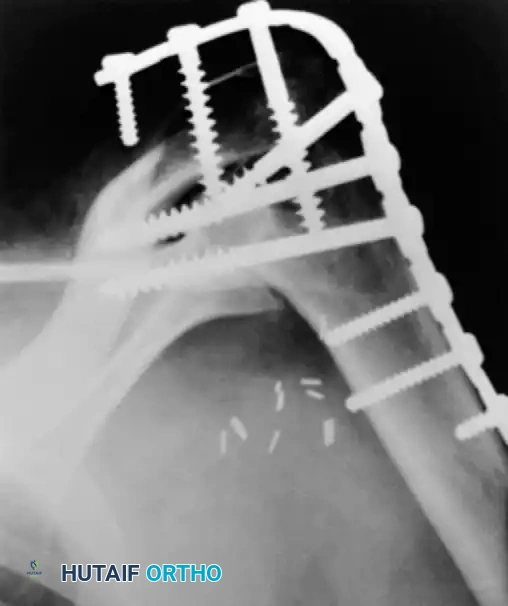

Radiographic confirmation of a contoured reconstruction plate achieving rigid acromiohumeral and glenohumeral compression.

In cases where soft-tissue coverage is extremely poor, or hardware prominence is a major concern, a screw-only construct may be utilized. This involves passing multiple large-fragment (6.5mm or 7.3mm) cannulated screws from the proximal humerus into the glenoid, and from the acromion into the humeral head. While this requires less dissection, it is biomechanically inferior to plate fixation and often necessitates postoperative spica casting.